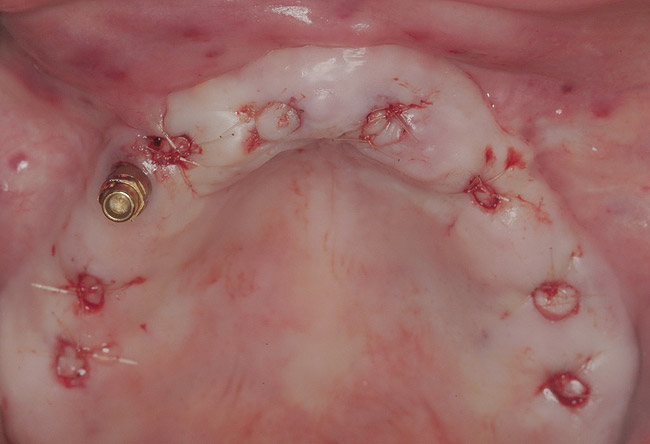

The surgery was initiated with eight mucoplasties using a disposable tissue punch. The autogenous, epithelialized grafts were maintained in aseptic conditions throughout surgery. After gentle irrigation of the implant sites with sterile saline, these eight tissue grafts were re-placed using resorbable sutures to prevent contamination of the implant sites and provide protection from the overlying treatment denture (Figure 22). The transitional denture was relieved, and a resilient reline was performed at the conclusion of surgery. The patient started a 10-day course of amoxicillin 500 mg three times daily, 1 hour prior to surgery, as well as a 6-day tapering dose of methylprednisolone 4 mg the morning of surgery. She was also prescribed an NSAID, etodolac 400 mg to be taken every 8 hours for 3 days, and a chlorhexidine gluconate rinse twice daily. She was advised to only wear the denture when absolutely necessary, and to always remove it before bedtime.

Figure 22  Resorbable sutures were used to re-place tissue grafts.

Figure 22